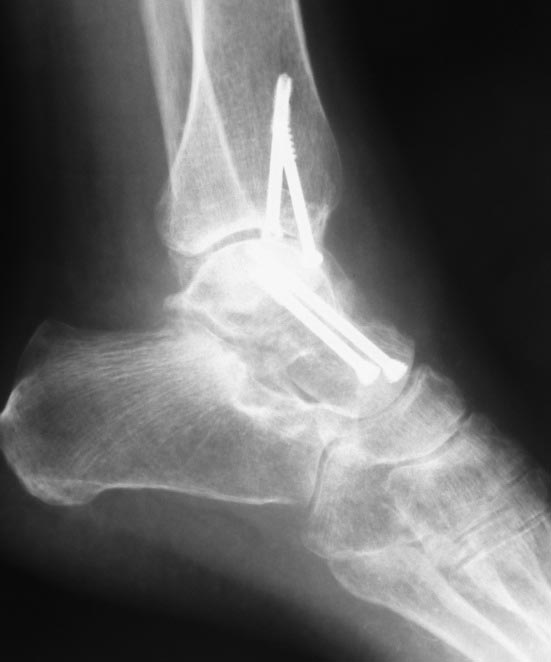

Два дня был без доступа к интернету. Во вложении недавний случай остеосинтеза оскольчатого переломовывиха таранной кости. Методика классическая. С анатомической репозицией и стабильной фиксацией. Без гипса после операции.